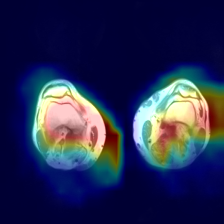

5.3.1 Coherence Score of Annotations

We chose the Fusion_Gate method for our application-grounded evaluation because it achieved the highest scores, albeit modest, in our functionally-grounded evaluation. Figure 7 presents all five distal myopathy cases side by side with their reference masks and the corresponding Fusion_Gate saliency maps, providing a direct visual comparison of true pathology versus model-identified regions. After converting each HCP’s annotations into binary masks, we computed the coherence between those masks and the Fusion_Gate saliency maps (Table 7). The large spread in RMA and RRA values demonstrates that even minor discrepancies in the ground truth mask can dramatically alter coherence scores, emphasizing the critical need for highly accurate, consensus ground truth annotations when using coherence as an interpretability metric. We then assessed each HCP’s overall annotation accuracy by RMA¯\overline{\mathrm{RMA}}over¯ start_ARG roman_RMA end_ARG and RRA¯\overline{\mathrm{RRA}}over¯ start_ARG roman_RRA end_ARG against the reference masks (first column of Table 8). RMA¯\overline{\mathrm{RMA}}over¯ start_ARG roman_RMA end_ARG indicates that HCPs reliably identify the general signal alteration regions, but their consistently lower RRA¯\overline{\mathrm{RRA}}over¯ start_ARG roman_RRA end_ARG confirms they lack the fine-grained precision of the expert in isolating the most critical subregions. Notably, when we compare these human baselines to the Fusion_Gate’s mean coherence scores (Table 5), the method’s RRA¯\overline{\mathrm{RRA}}over¯ start_ARG roman_RRA end_ARG surpasses that of all but two HCPs. In other words, the attention mechanism could faithfully highlights the single most important pixel than most individual annotators. Lastly, the comparatively low RMA¯\overline{\mathrm{RMA}}over¯ start_ARG roman_RMA end_ARG and RRA¯\overline{\mathrm{RRA}}over¯ start_ARG roman_RRA end_ARG values in the second column of Table 8, which quantify how well the Fusion_Gate saliency maps align with each HCP’s own mask, reveal that even our best interpretability method still falls short of expert-level delineation. In other words, although attention-based saliency can highlight broadly relevant regions, it does not yet match the clinical precision of HCPs’ annotators. This gap underscores that, despite promising advances, more work is needed before automated explanations can achieve the same fidelity as experienced radiologists.

Refer to caption

(a) Image 1

(b) Ground truth Mask 1

(c) Saliency Map 1

(d) Image 2

(e) Ground truth Mask 2

(f) Saliency Map 2

(g) Image 3

(h) Ground truth Mask 3

(i) Saliency Map 3

(j) Image 4

(k) Ground truth Mask 4

(l) Saliency Map 4

(m) Image 5

(n) Ground truth Mask 5

(o) Saliency Map 5

Figure 7: Image instances of the distal myopathy dataset with their corresponding reference masks and saliency maps.